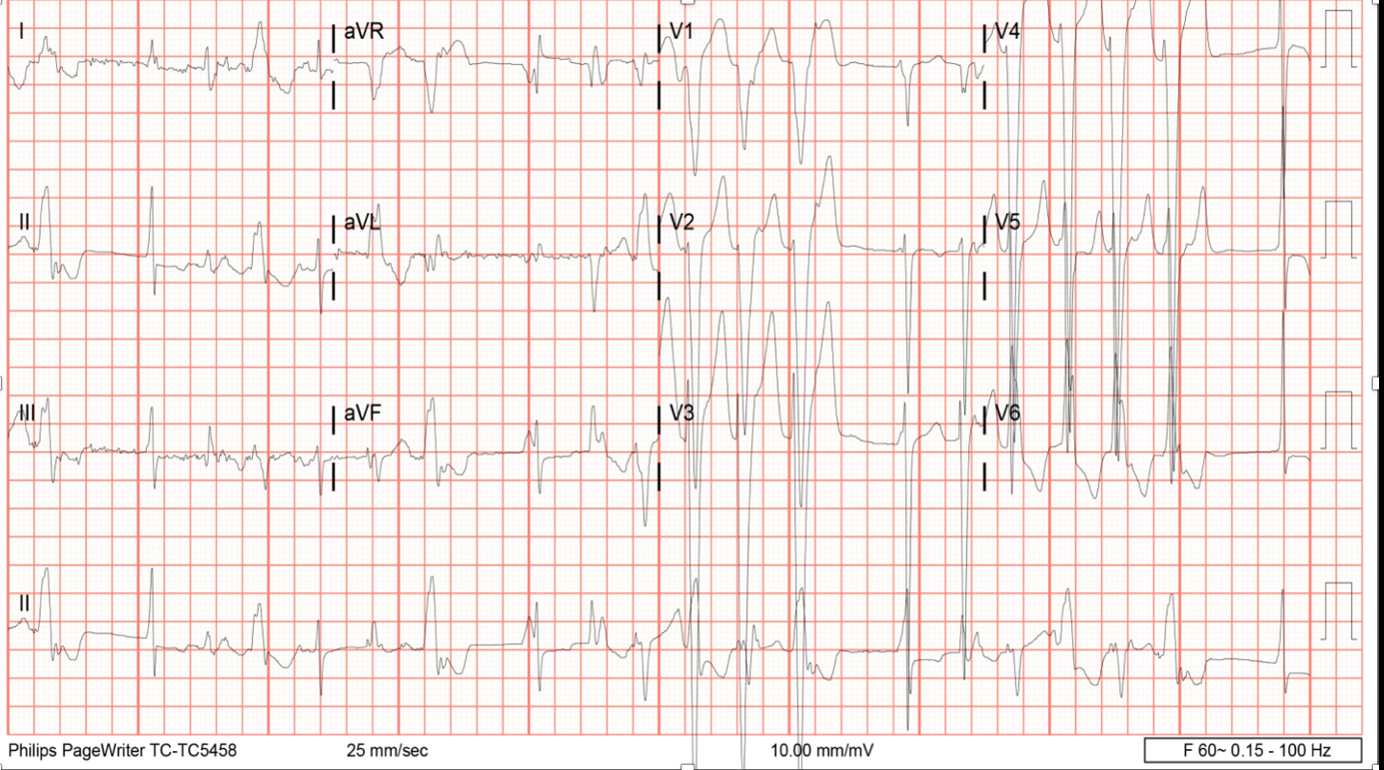

A 33-year-old man with WPW syndrome status post ablation, hypertension, and paroxysmal atrial fibrillation presented to the emergency room with dizziness, decreased exercise tolerance, and fatigue. Blood pressure was 138/107 mmHg, heart rate 138 bpm, and normal oxygen saturation. Troponin I was negative, and EKG showed new wide complex tachycardia, LBBB, multifocal PACs, and PVCs. The echocardiogram noted severe LVH, diffuse hypokinesis, and a newly reduced LVEF of 15-20%, with LVEDD of 6 cm. Cardiac MRI had no evidence of infiltrative disease, infarct, or fibrosis. Exercise SPECT was negative for ischemia. He was discharged on a beta blocker, ACE inhibitor, and MRA. He had recurrent VT and PVCs despite being on amiodarone. Atrial fibrillation was controlled after PVI ablation. LV function remained <35%, and a dual-chamber ICD was implanted for primary prophylaxis.